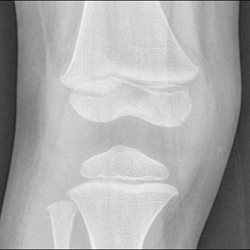

Potential osteomyelitis of the knee.